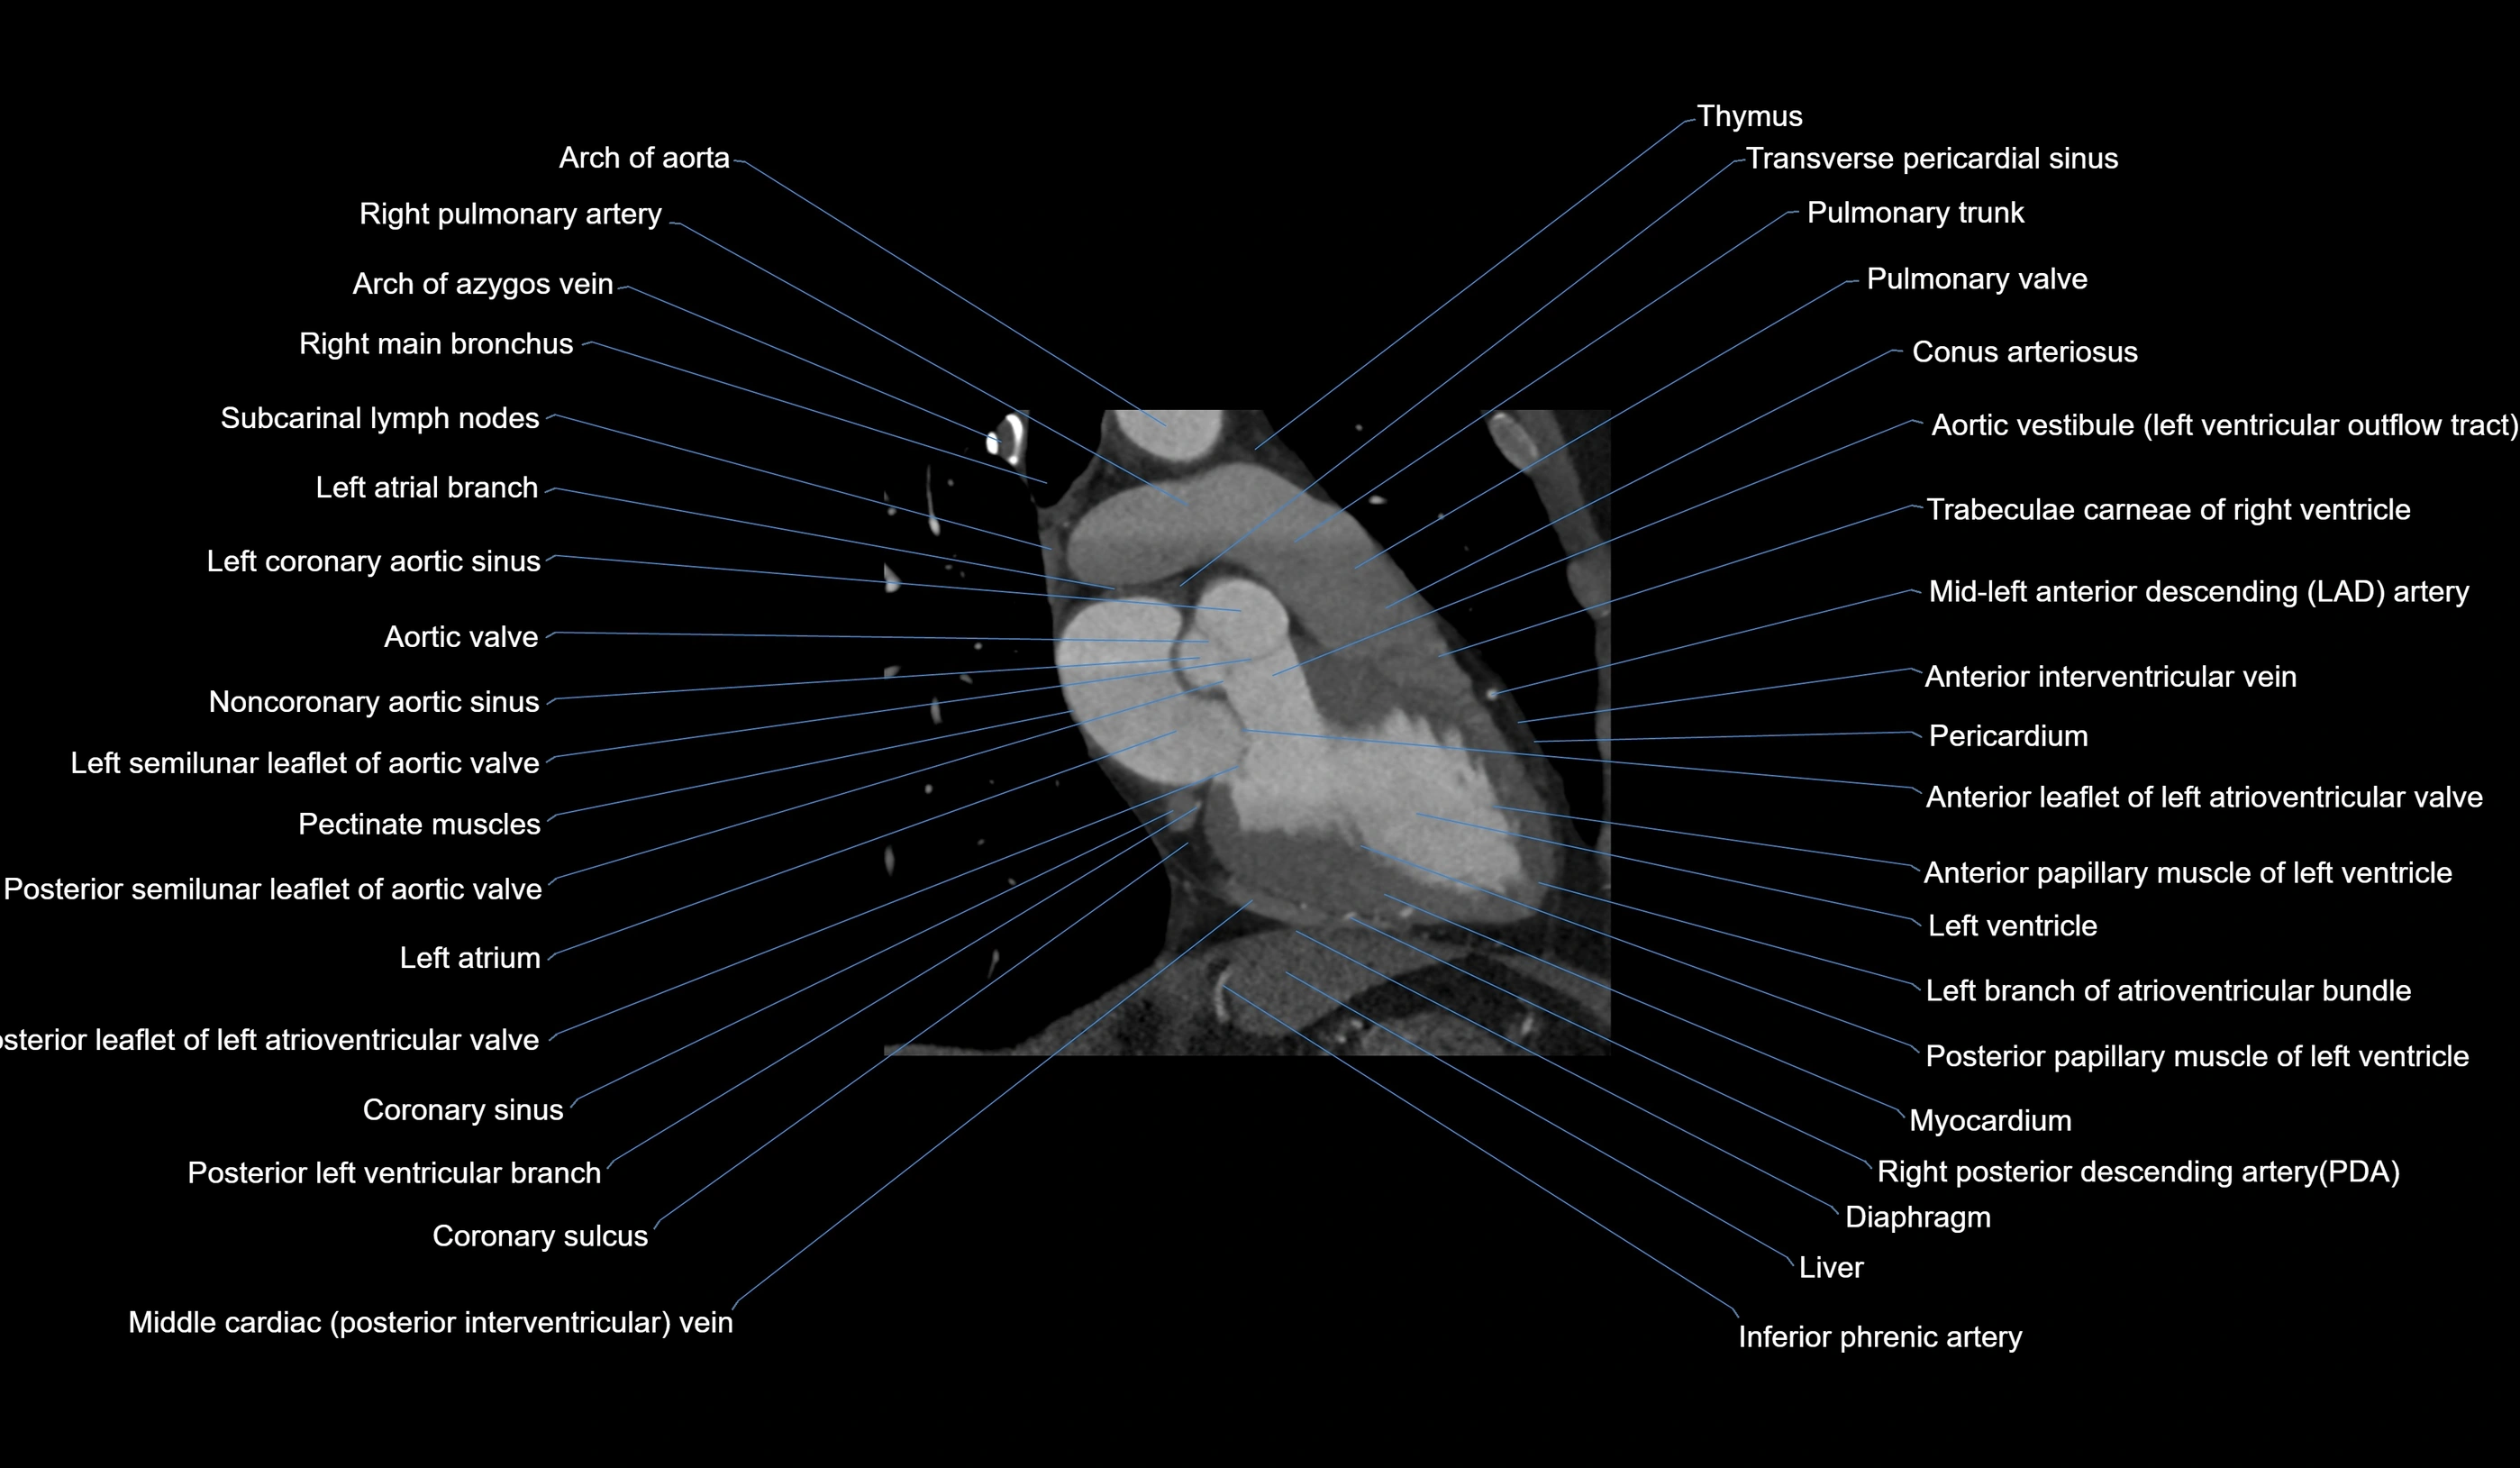

CT images